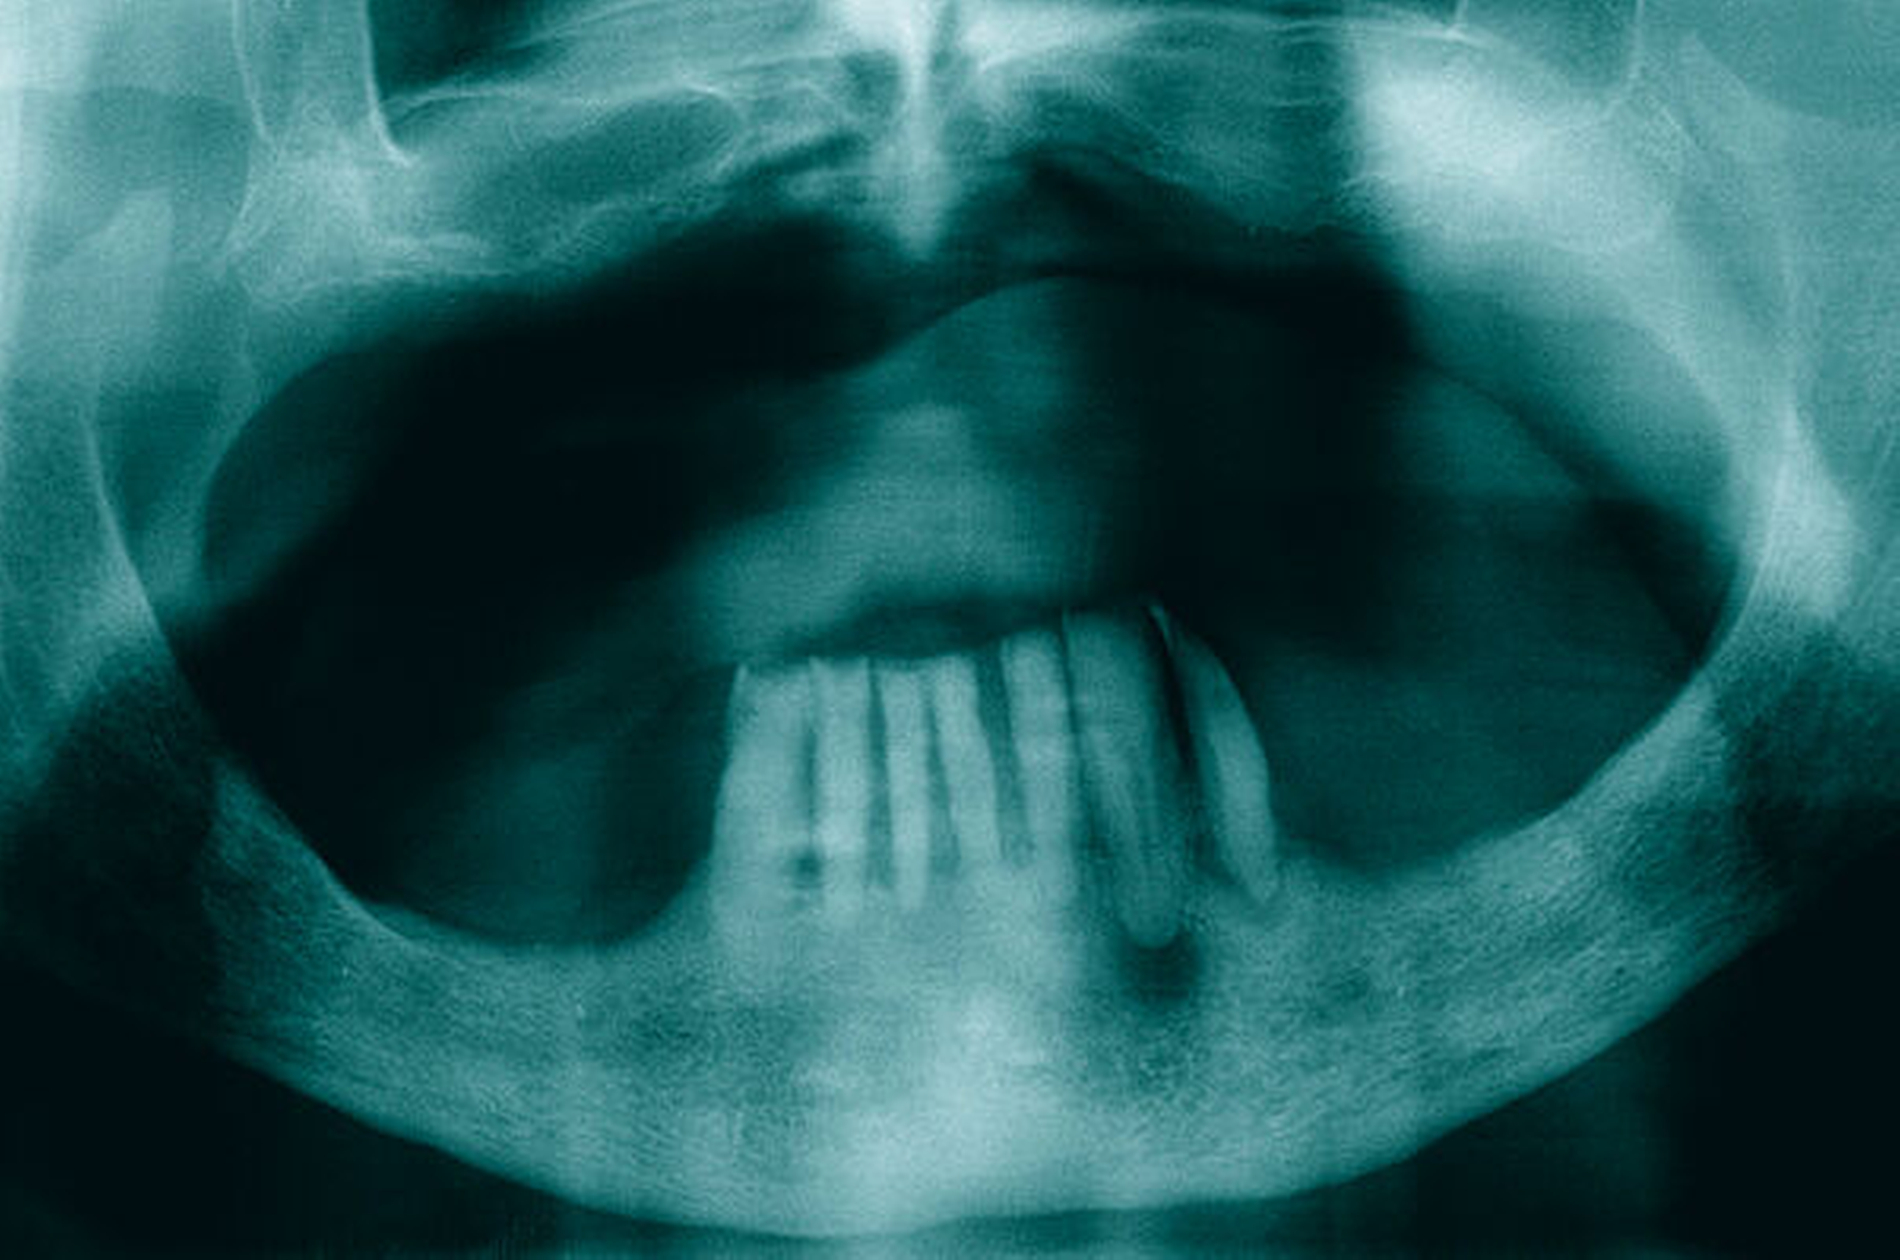

Die klinische und radiologische Untersuchung (Abbildungen 1 und 2) zeigte einen zahnlosen Oberkiefer sowie eine nicht erhaltungswürdige, stark parodontal geschädigte anteriore Restbezahnung im Unterkiefer. Aufgrund der bekannten schweren Hämophilie B (Faktor-IX-Aktivität < 1 Prozent) erfolgte die Vorstellung des Patienten in der betreuenden Gerinnungsambulanz in der Abteilung für Hämatologie, Onkologie und Palliativmedizin der Universität Rostock. In interdisziplinärer Absprache wurde unter Berücksichtigung des operativen Behandlungsbedarfs ein Faktorsubstitutionsplan für den Patienten erstellt (Tabelle). Aufgrund der Komplexität des Behandlungsprotokolls fand die weitere Therapie unter stationären Bedingungen statt.

Am Aufnahmetag wurde die erste Substitution mit 1800 I.E. humanem Blutgerinnungsfaktor IX (Berinin®, CSL Behring, Marburg) mit anschließender Faktor-IX-Aktivitätskontrolle (angestrebte Aktivität: 20 Prozent) zur Kontrolle des Therapieansprechens durchgeführt. Nach Rücksprache mit den Kollegen der Gerinnungsambulanz konnte die geplante Extraktion der Zähne 43, 42, 41, 31, 32, 33 und 34 am Folgetag unter erneuter vorheriger Substitution und Faktor-IX-Aktivitätskontrolle (Zielwert > 60 Prozent) sowie antibiotischer Abschirmung (i. v. 3 x 3 g Ampicillin/Sulbactam) durchgeführt werden.